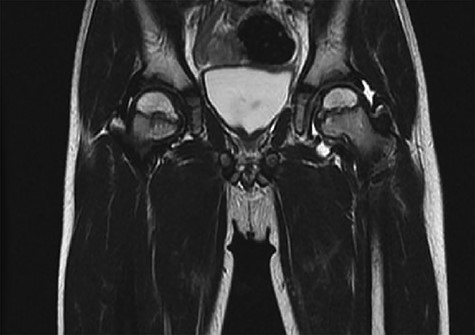

CT hips reported a well-defined lesion seen bilaterally in the neck of femur anterior infero-medial aspect, more prominent on the left side measuring 7 x 3 mm on left side both in coronal (Fig. 3) and axial (Fig. 4) views. On the right side, other lesion measuring 2 x 1 mm (Fig. 5) seen in coronal view. These two lesions are well defined with a sclerotic border with a small cortical defect. The lesion shows fat density. The symmetrical appearance of the lesion combined with the fat density and location suggest the diagnosis of synovial herniation pit. MRI Pelvis revealed minimal left hip joint effusion with loculated fluid seen along the trochanteric bursa with the largest measuring 0.9 x 1.5 cm (Fig. 6, 7).

Showed coronal cut of CT hips demonstrating the synovial pit prominent right side.